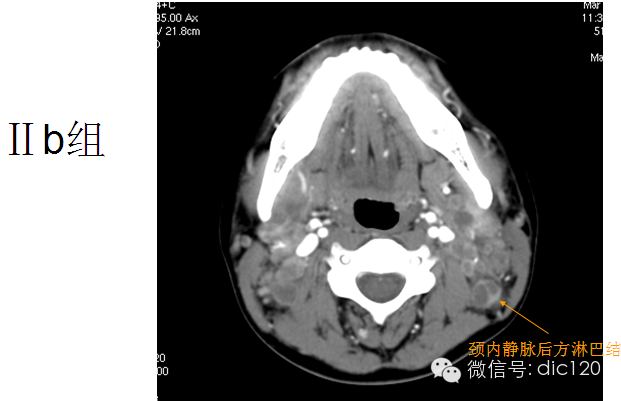

Ⅱ区包括颈静脉上组淋巴结,位于颈内静脉上1/3和副神经上部周围。自颅底一直延伸至颈动脉分叉或舌骨体下缘。影像学角度采用颈内静脉后缘做为Ⅱa和Ⅱb的分界。Ⅱ区接受来自面部、腮腺及下颌下、颏下和咽后淋巴结的淋巴管,也直接接受来自鼻腔、咽、喉、外耳道、中耳及舌下腺和下颌下腺的集合淋巴管,是鼻腔、口腔、咽、喉和涎腺肿瘤发生隐匿转移的高危区域,其中Ⅱb与口咽或鼻咽的肿瘤关系更为密切。